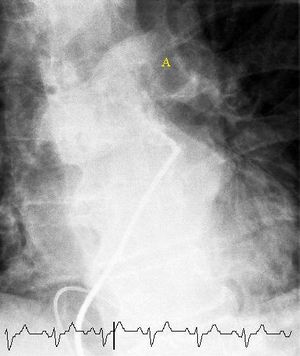

(A) After inhalation of 20 mCi of Xenon-133 gas, scintigraphic images were obtained in the posterior projection, showing uniform ventilation to lungs.

(B) After intravenous injection of 4 mCi of Technetium-99m-labeled albumin, scintigraphic images shown here in the posterior projection. This and other views showed decreased activity in multiple regions.

مسح التهوية والتروية الرئوي هو شكل من التصوير الشعاعي التشخيصي هدفه تقييم التروية والتهوية في الرئتين ويستخدم في تشخيص الانصمام الرئوي، مبدأ عمله هو كالتالي:

- الجزء المتعلق بالتهوية يتم من خلال جعل المريض يستنشق هواء يحتوي على غاز الزينون أو التكنيشيوم.

- الجزء المتعلق بالتروية يتم فحصه من خلال حقن المريض بالتكنيشيوم أو أي صبغة مشعة.

- يتم تصوير الصدر بكاميرا غاما عقب ذلك.

استخدام هذه التقنية أقل شيوعاً من الالتصوير الطبقي المحوسب للرئة وذلك لعدم توفر هذه التقنية في كل المستشفيات كما أن دقة الالتصوير الطبقي المحوسب للرئة أصبحت أعلى، تستخدم هذه التقنية حالياً في حالات الحمل والحساسية للصبغات المشعة أو اليود المشع.[21]